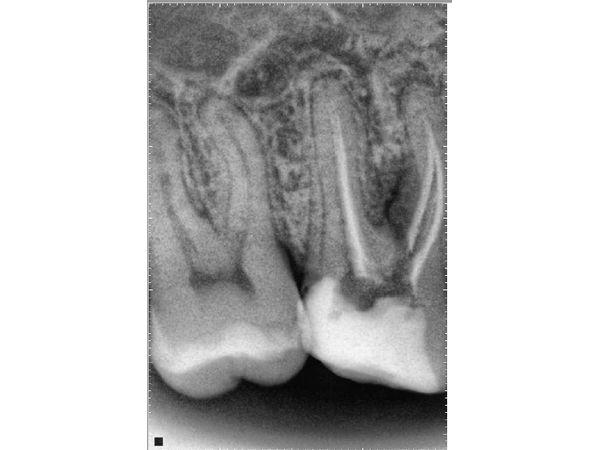

По результатам компьютерной томографии верхней и нижней челюстей:

- очаги воспаления в области верхушек 36-го зуба вплоть до области разделения корней;

- микротрещина во втором медиально-щёчном канале.

Периодонтит, перфорация в 36-м зубе.